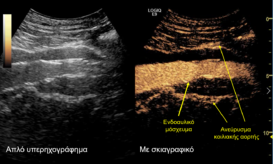

Νέα, καινοτόμος τεχνική για την αντιμετώπιση υπερνεφρικού ανευρύσματος της αορτής εφαρμόστηκε στο Ιατρικό Κέντρο Αθηνών, για πρώτη φορά στην Ελλάδα,...